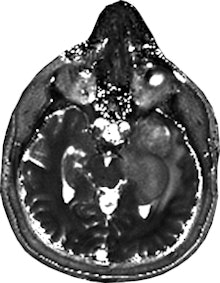

Dr. Siegfried Trattnig sees a "paradigm shift" from qualitative to quantitative imaging. Image courtesy of Medical University of Vienna/E. Hammerschmid.The results using an advanced MR imaging protocol and MR fingerprinting showed that the T1 and T2 mapping of tissue provided by fingerprinting was "better visualized" than in the standard protocol, said Trattnig, medical director of the university's Centre of Excellence in High Field MR and the chairman of the European Imaging Biomarkers Alliance (EIBALL). The testing was conducted using five patients with malignant brain tumors and an equal number with low-grade gliomas.

"It's my impression that we see more changes by using MR fingerprinting based on T1 and T2 maps on this quantitative data. And looking into the tumor, you see more details that are not shown on standard imaging," he explained, emphasizing that the results of the Austrian university's 2015 tests are only preliminary.